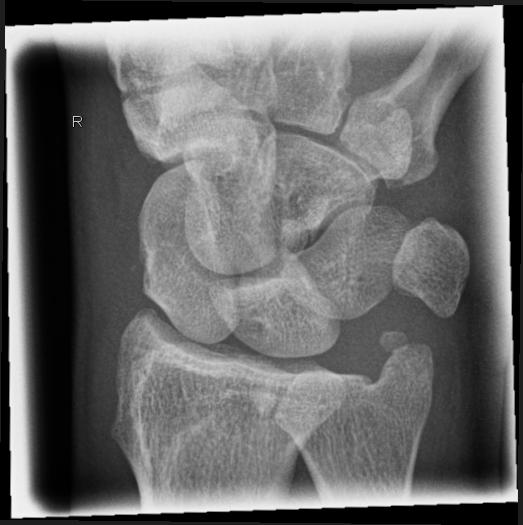

Handgelenk seitlich

Beurteilungskriterien

- Neigung der distalen Radiusgelenkfläche in der Sagittalebene: 10 – 15°

- Kontinuierliche Verlängerungsachse durch Radius, Lunatum, Capitatum und Os metacarpale III. Kontinuität von Handrücken und Unterarmrückfläche (Luxation, nicht-exakte Einstellung? -> Proc.styloideus ulnae im hinteren Radiusdrittel?)

- Scapholunärer Winkel 30 – 60°

- Verstreichen und Ventralverlagerung der volaren Fettstreifen vor dem M.flexor digitorum profundus und M.pronator quadratus

- Grundsätzlich gilt: unklare Verhältnisse -> CT-Indikation

Beispiele

Smith-Fraktur (2) volare Fragmentabkippung

Colles- Fraktur (2) dorsale Fragmentabkippung

Chauffeur-Fraktur (2) radialer Keilbruch

Barton-Fraktur (2) intraartikulär, dorsales Kantenfragment

Reversed Barton-Fraktur (2) intraartikulär, volares Kantenfragment